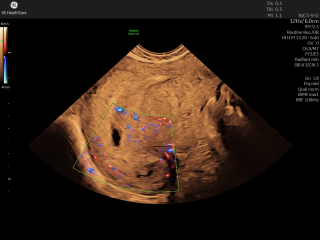

Sonnyelodie88 · 27/02/2026 11:50

Have had an early scan, first midwife said twins, second said only a bleed is possible - confused - see scan photo. thoughts anyone??

How far along were you when you had the scan. Its definitely too early to really have an opinion. If they are sacs there is nothing in them at this stage that I can see and the bottom dark spot could be part of a bleed. The only way your going to know is to go back for a scan a little later on, say closer to 8 weeks gestation.

ToKittyornottoKitty · 28/02/2026 14:21

It looks like it’s just too early to say. How far along do you think you are?